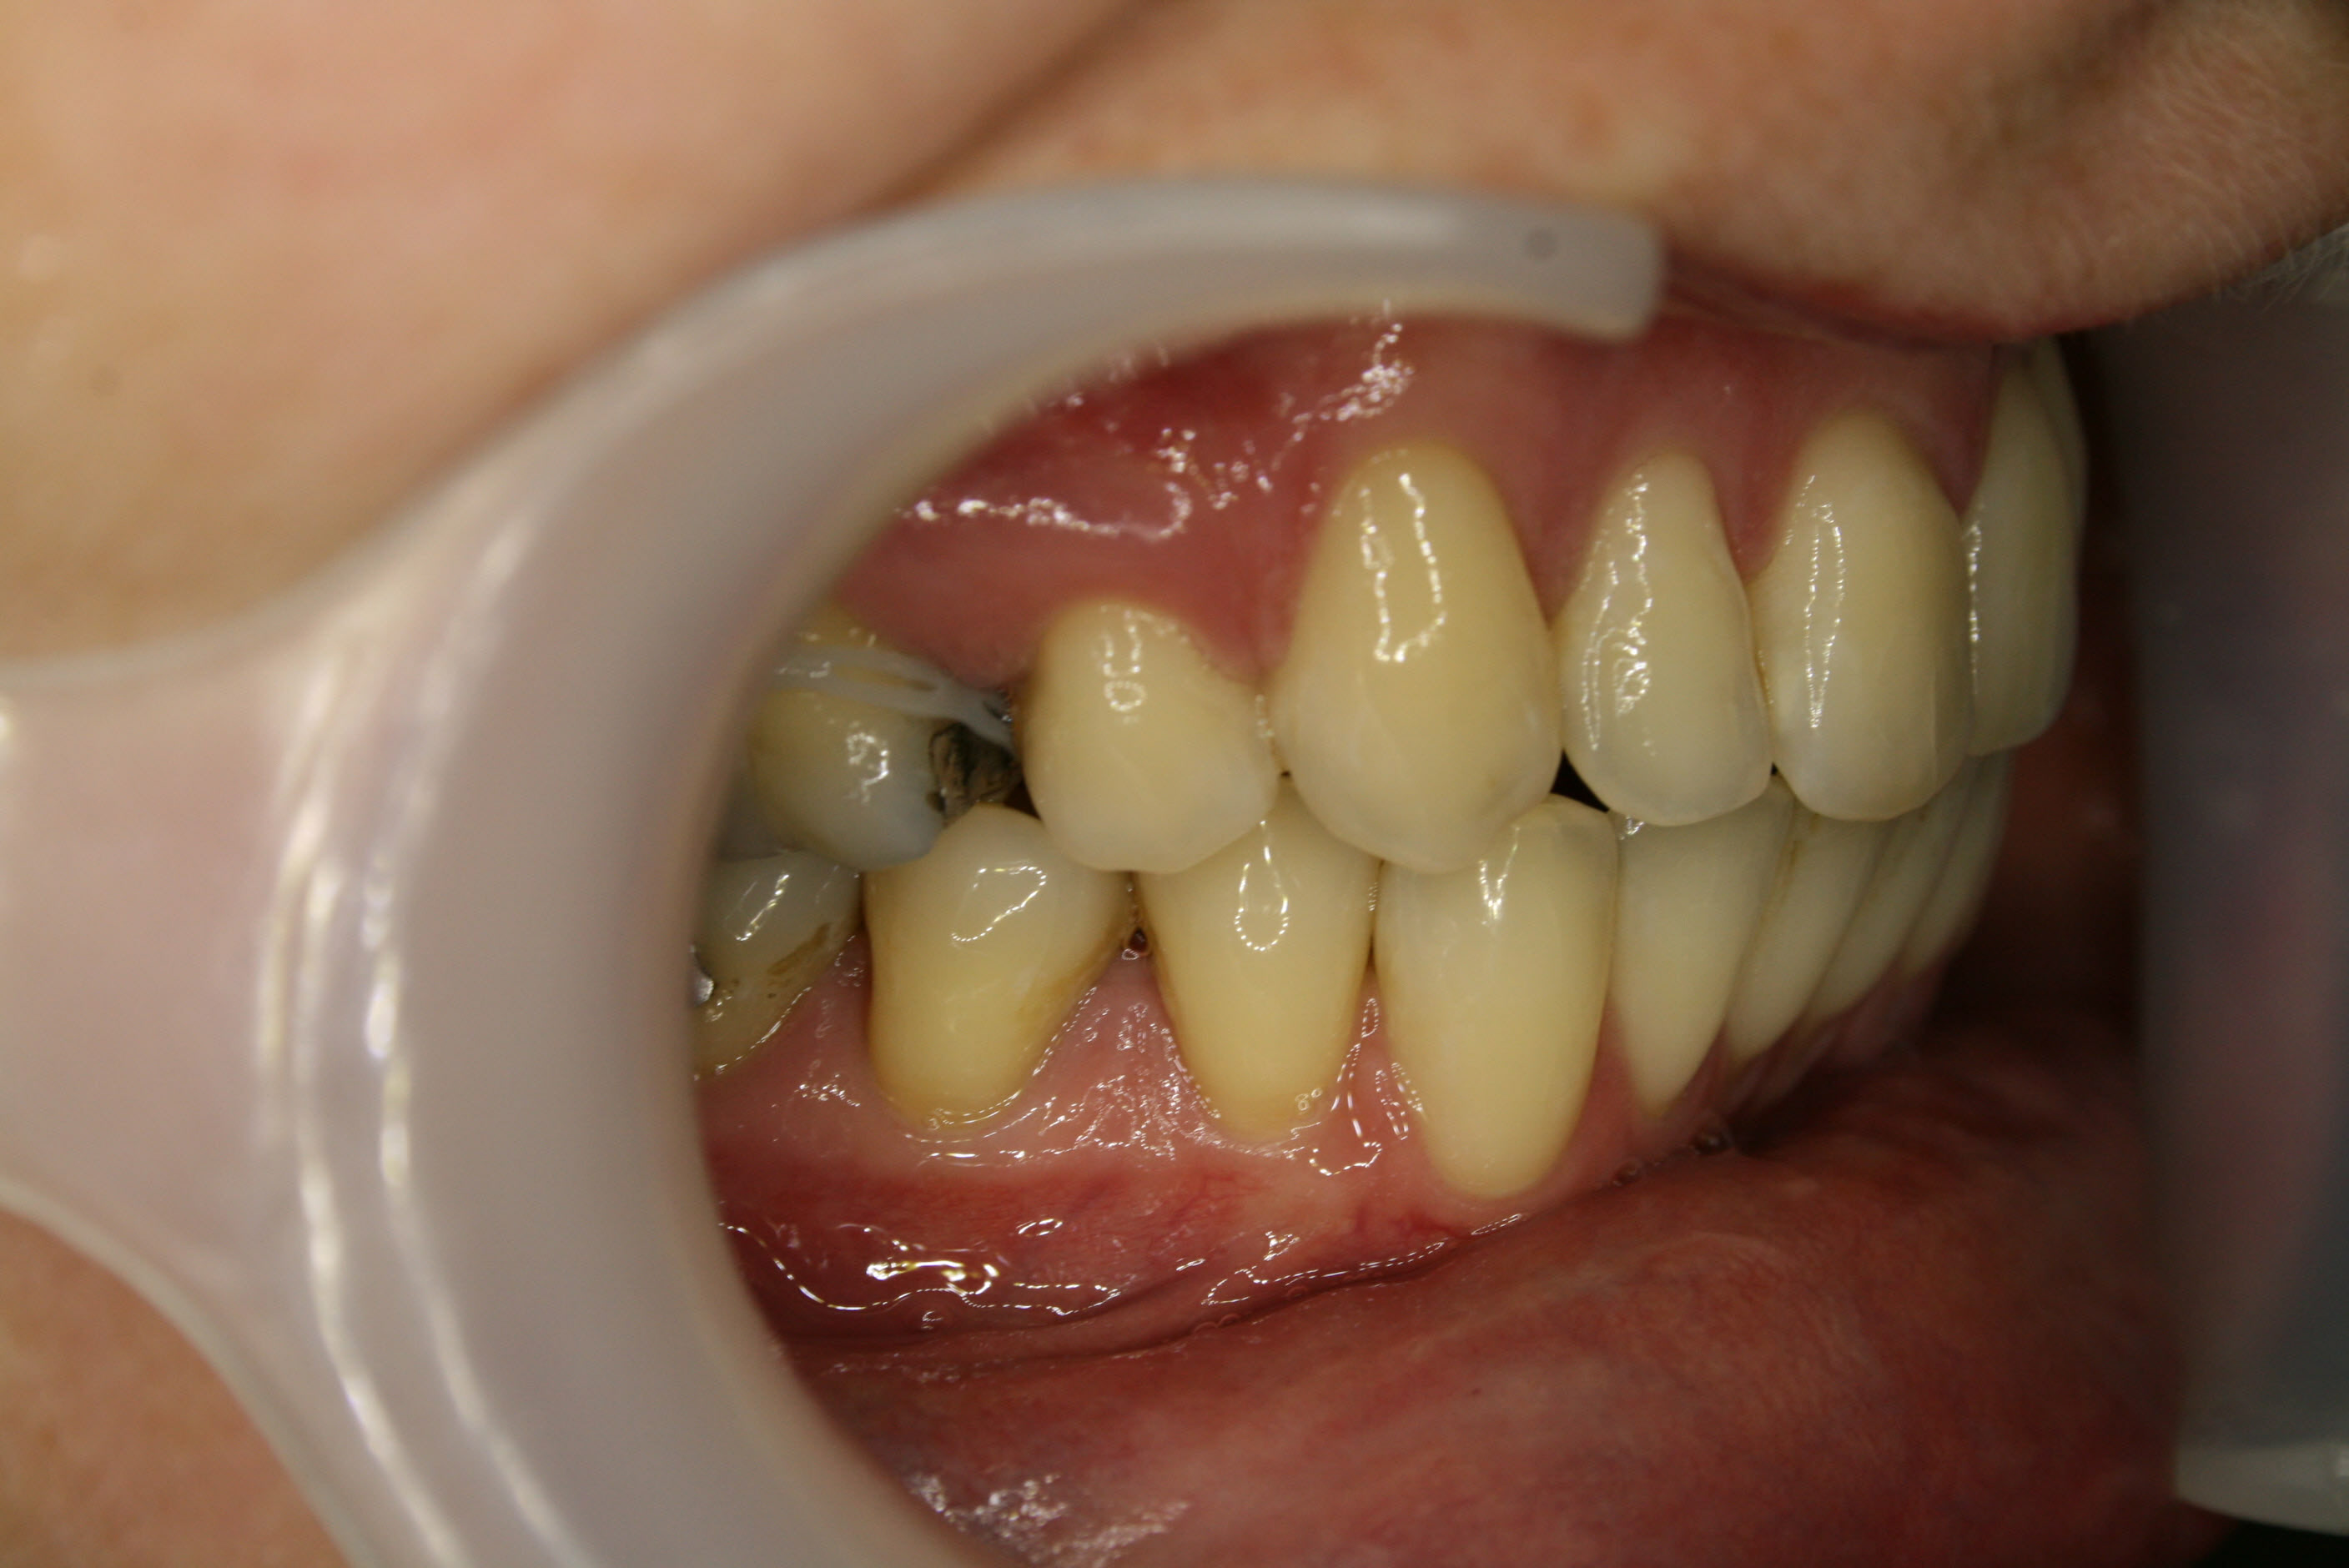

Die ersten kleinen Backenzähne sind bereits entfernt und die festsitzende Zahnspange ist eingesetzt, in diesem Falle quasi unsichtbar auf der Innenseite der oberen Schneidezähne. Es ist wesentlich, daß die Lücken nur von vorne her geschlossen werden. Dies wurde sichergestellt, indem die Zähne hinter den Lücken über temporäre kleine Implantate am Gaumendach verankert wurden. In der Bildsequenz ist der Behandlungsfortschritt zu erkennen; der Lückenschluß war nach 1½ Jahren erreicht.

Lückenschluß in der Seitenansicht; hier ist gut zu erkennen, daß es gelungen war, den Lückenschluß von vorne her und achsengerecht auszuführen.